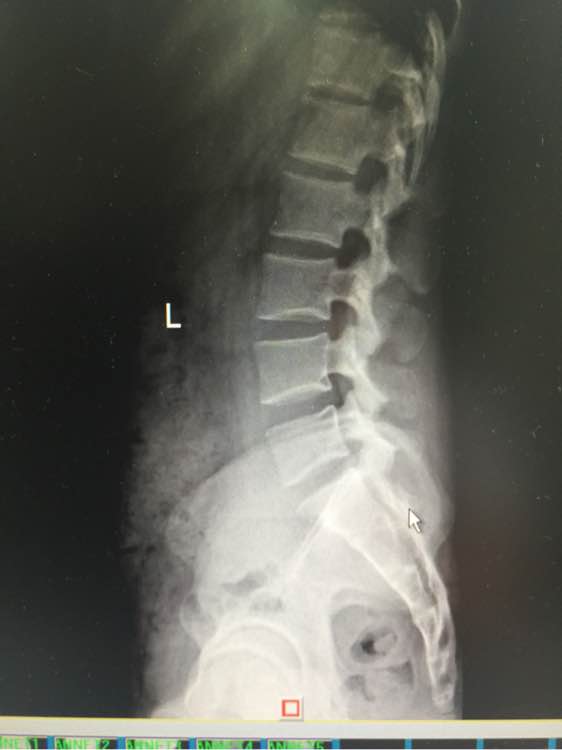

吧友们帮我看看,寰枢椎关节半脱位,供血不足

站不稳,坐不稳,走不稳, 做什么都飘飘的,走路不平衡,躺着还有塌陷的感觉 除了早上醒来 舒服点,越到下午越来越严重, 感觉无时无刻人就像在船上 左右摇晃的 偶尔更换体位 耳朵鼓鼓的 (这是国庆最严重时候 现在还是晕,没那么晕了,但还是没好 以下一直影响生活到现在)尿尿要扶墙,洗澡不敢洗太久 靠着墙,刷不了牙,刷牙晃动脑袋也更晕,有时候晚上坐着就犯晕,血压高,145 95以上 躺着血压就正常

看你的片子觉得不是你说的那么严重,做什么工作,平时注意吧